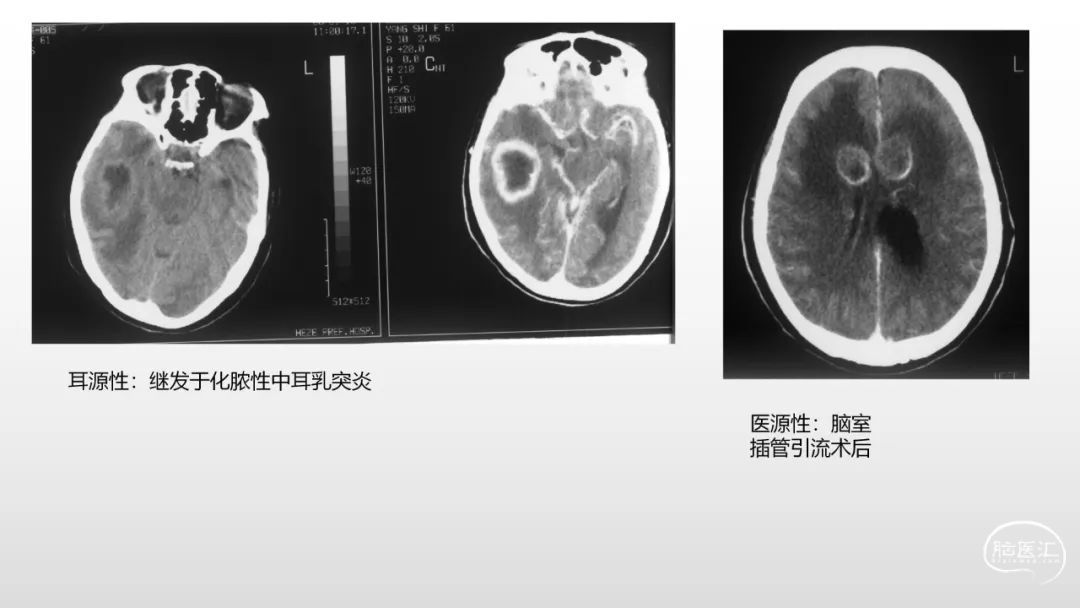

颅脑影像诊断基础知识讲座:感染和免疫性疾病1